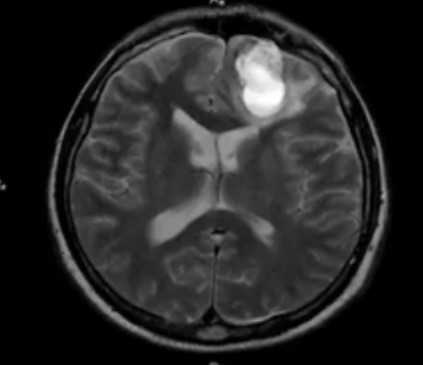

Внутримозговая гематома травматического характера на МР-снимке

В результате МРТ получают множество послойных снимков в трех взаимно-перпендикулярных плоскостях. На изображениях видят контуры тканей, сравнивают показатели с нормой, выявляют отклонения и признаки патологических изменений. Все данные отражают в заключении.

По результатам МРТ лицевого отдела черепа выявляют:

- аномалии развития;

- последствия травм (растяжения и разрывы связок, повреждения суставных элементов, сосудов, мышц, патологическое скопление жидкости и пр.);

- нарушение строения околоносовых пазух (деформации, новообразования и пр.);

- опухоли добро- и злокачественной природы, метастазы (окончательный диагноз — по результатам гистологии);

- изменения воспалительного характера (абсцесс, флегмону и пр.).